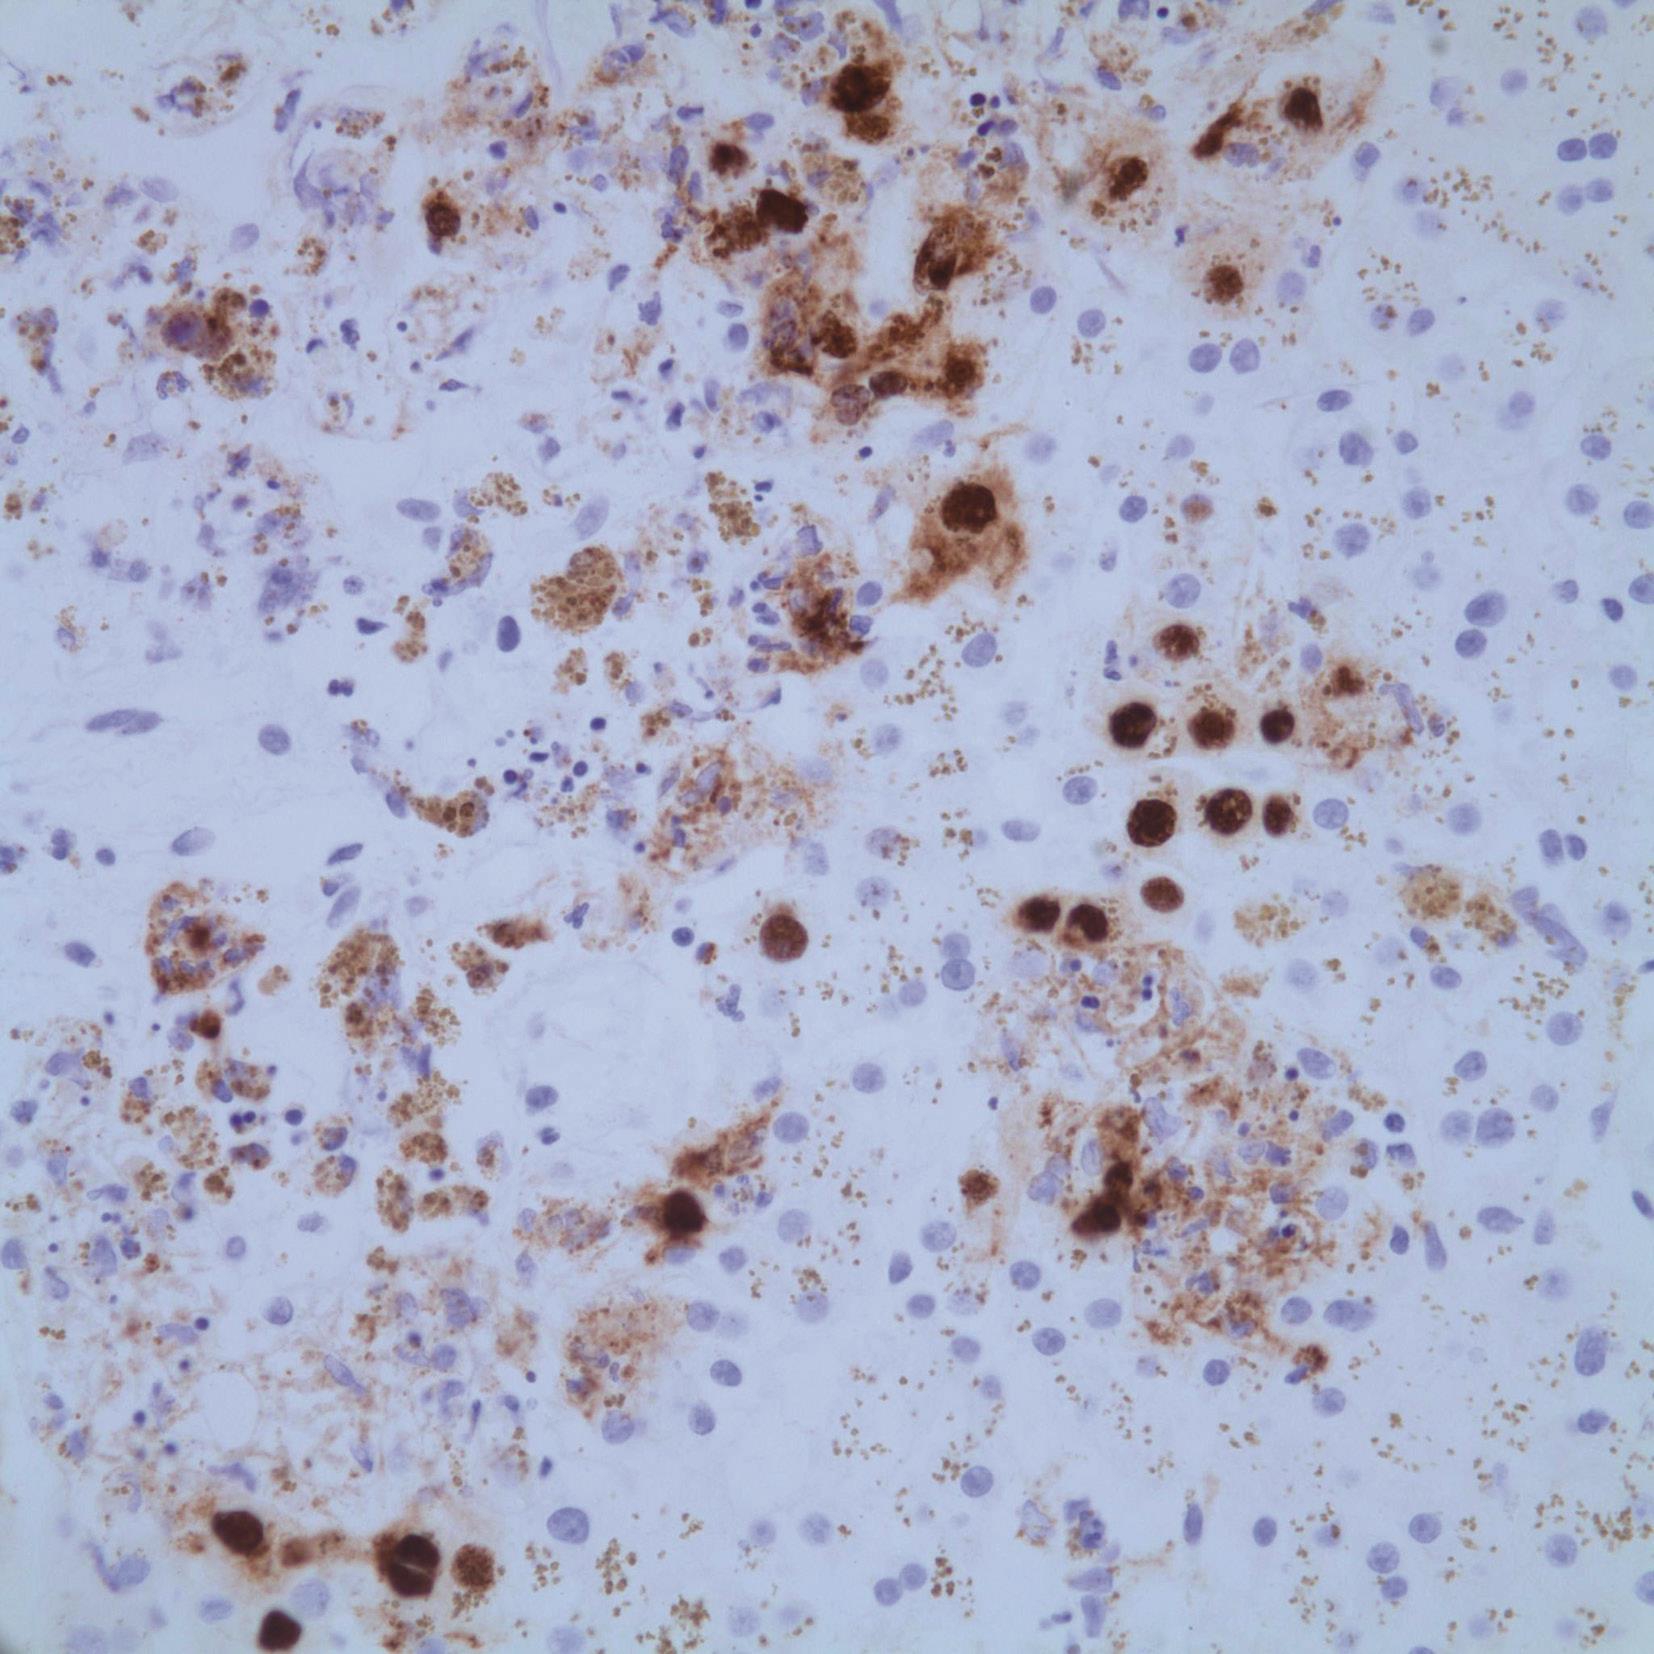

EB病毒为非亲肝病毒、自限性疾病。病理变化为肝小叶炎轻微,肝细胞淤胆不常见,肝窦内单个核细胞呈串珠样排列,汇管区浸润的炎症细胞包括B淋巴细胞、T淋巴细胞和NK细胞,可见异型的淋巴母细胞、静脉内皮炎,可伴肝细胞脂肪变、肉芽肿和胆管系统损伤(图4-18-1)。EB病毒编码的小RNA(EBER)原位杂交证实病毒(图4-18-2)。

图4-18-2 肝组织EB病毒原位杂交染色